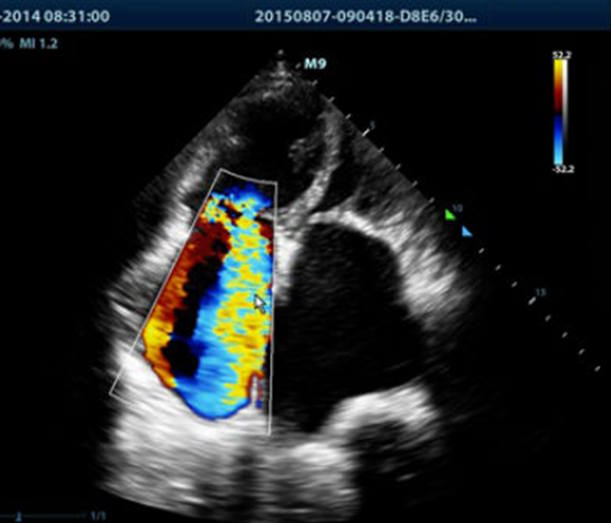

Imagen de una ecocardiografía

La **ecocardiografía**, también conocida como ecocardiograma o eco, es un examen médico que utiliza ondas sonoras para crear imágenes del corazón. Permite visualizar la estructura y función del corazón, incluyendo sus válvulas y el flujo sanguíneo. Es una prueba no invasiva y segura, utilizada para diagnosticar diversas enfermedades cardíacas y evaluar el funcionamiento del corazón.

La ecocardiografía utiliza ondas sonoras de alta frecuencia (ultrasonido) para generar imágenes del corazón. El procedimiento implica la aplicación de un gel conductor en el pecho del paciente y el uso de un transductor para emitir y recibir ondas sonoras. Estas ondas se reflejan en las estructuras del corazón, creando ecos que son captados por el transductor y convertidos en imágenes en tiempo real en un monitor.